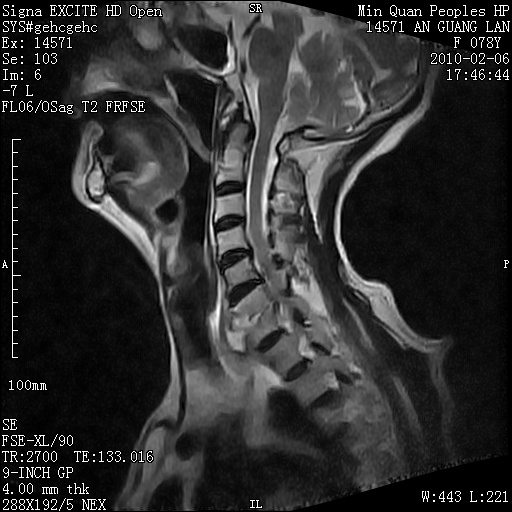

标题: MRI2763:C6、C7椎体病变性质?

f,78y,颈部与双上肢阵发性剧痛40余天。ct可见c6、c7椎体虫蚀样破坏,其间椎间隙变窄(没有图片资料可供上传)。

考虑椎体结核并椎旁脓肿。

考虑:c6/7椎体结核并椎旁脓肿形成,建议增强扫描。